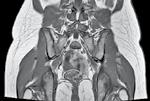

Rolul analizării răspunsului inflamator sistemic în funcție de momentul operator la pacienți tratați chirurgical pentru fracturi pertrohanteriene

The role OF systemic inflammatory response analysis based ON surgical timing IN patients treated FOR pertrochanteric fractures

Summary: This article studies the relationship between the systemic inflammatory response and the timing of surgery in elderly patients with pertrochanteric fractures. The results show that patients who underwent surgery within 48 hours had a significantly lower inflammatory response, as indicated by lower IL-6 levels, and experienced fewer postoperative complications compared to those who had delayed surgery. The study suggests that IL-6 could serve as a prognostic marker for postoperative outcomes, emphasizing the importance of early surgery in improving recovery.

Fracturile de șold reprezintă o problemă de sănătate publică, din cauza impactului acestora asupra vieții pacienților, având un caracter debilitant, dar și din cauza costurilor ridicate asociate cu tratamentul fracturii și al complicațiilor sale, în special la pacienții vârstnici [1, 2]. Aceste fracturi pot fi deosebit de periculoase, deoarece adesea exacerbează patologii preexistente, ducând la creșterea morbidității [3]. Deși este larg acceptat faptul că fracturile de șold necesită o intervenție chirurgicală cât mai devreme, momentul optim rămâne dezbătut [4, 5]